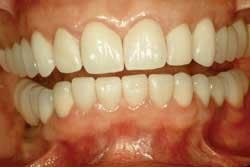

The excess cement is removed with a Bard Parker 12B scalpel blade. Minimal polishing is done with Sof-Lexâ„¢ Extra Thin Superfine Discs (3M ESPE) and Flexibuffsâ„¢ with Porcelize polishing paste (Cosmedent). The remaining veneers are seated in pairs following the same protocol (Fig. 9).

These steps have worked well for me in my practice. The halogen curing lights have withstood the clinical tests of time. Time will tell if the LED curing lights, with shorter curing times, will be as successful. While some dentists may feel comfortable seating multiple veneers at one time, my concern is improper seating and marginal adaptation that may be affected by tight interproximal contacts, drifting of the veneers, or both. By seating two veneers at a time, the clinician can make certain the restorations are completely seated the first time, reducing the likelihood of costly and timely replacements. I usually schedule approximately 15 to 20 minutes per veneer, depending on the patient. For example, if it is a maxillary, lingual-wrap veneer cemented with the Tack & Wave technique and using an LED curing light, it takes less time. The majority of time is spent trying in the veneers and preparing for the actual cementation.

With proper preparation design and cementation techniques, dentists can provide patients with one of the best-fitting, longest-lasting, esthetic porcelain restorations available. Profitability often can be measured by a satisfied patient’s smile and time-saving procedures.